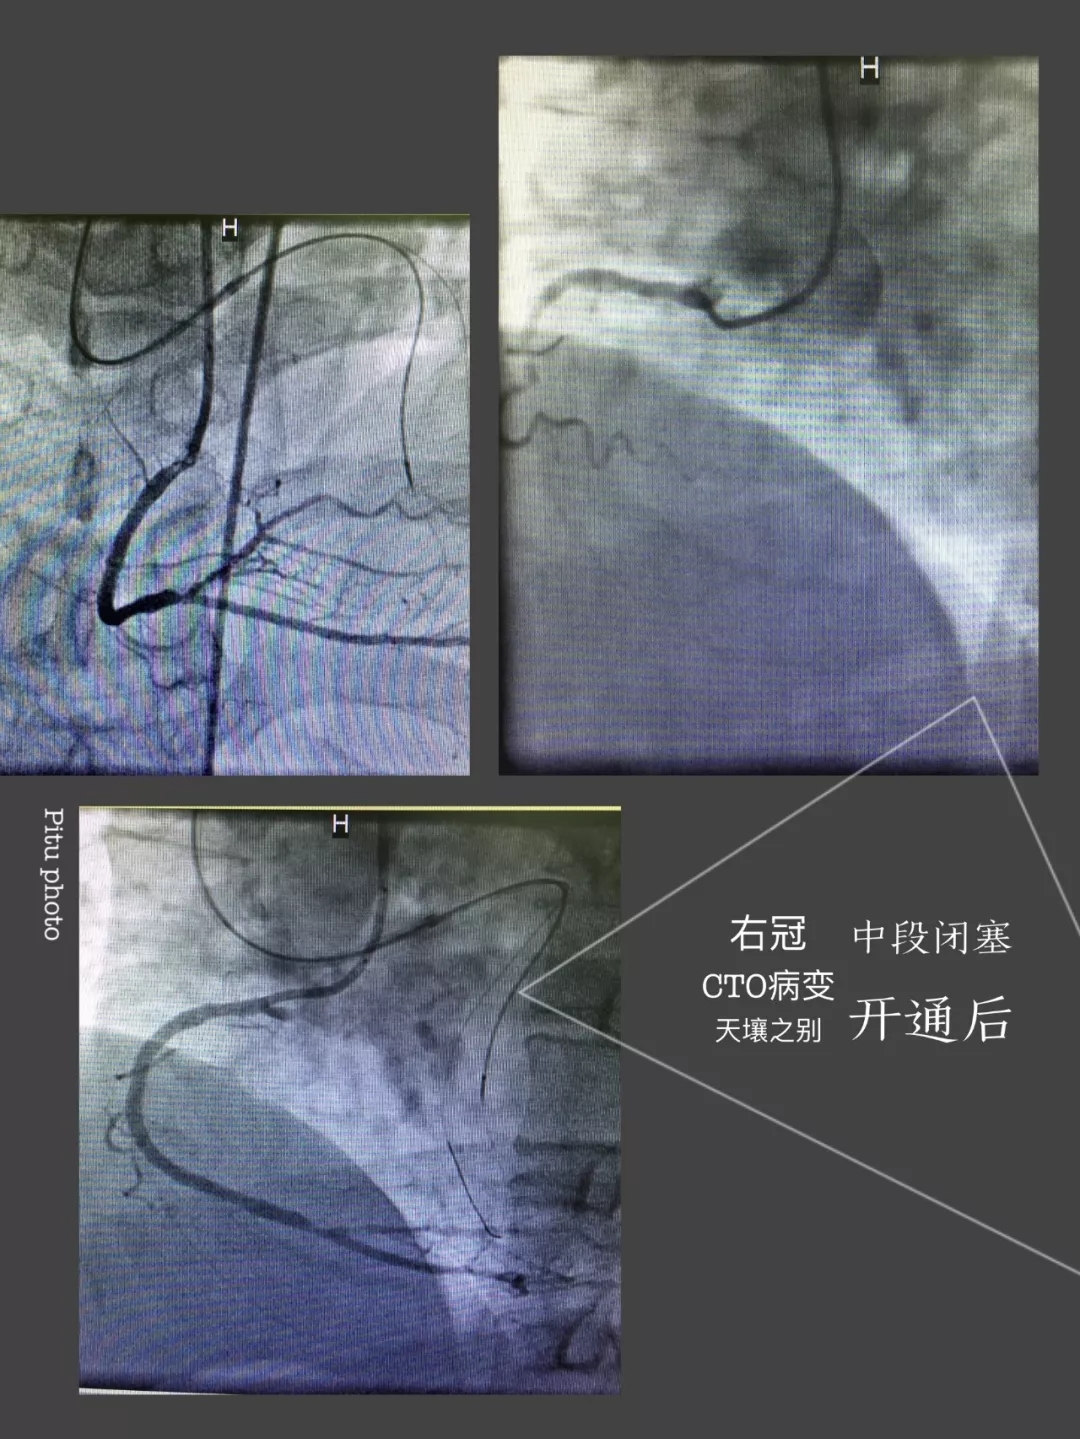

心内三完成啄木鸟 首例逆向开通冠脉CTO病变